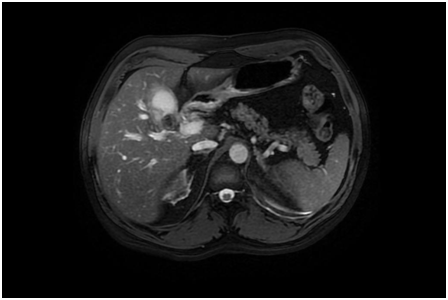

A 51-year-old Caucasian male presented to our emergency department with yellow skin, eyes and light colored stools which had developed over 2-3days along with some loss of appetite & weight. He was not complaining of any pain or change in his bowel or bladder habits. There was no associated fever, pain in the abdomen, nausea/vomiting or pruritus. His past medical history was significant for Diabetes Mellitus and Hyperlipidemia, which were being managed medically. The patient only admitted to occasional social drinking. Labs revealed an Obstructive Jaundice pattern with direct hyperbilirubinemia and elevated liver enzymes. Previous records showed normal LFTs despite statin therapy for Hyperlipidemia. US abdomen showed presence of gallstones and GB sludge. CT Abdomen done in the emergency room showed multiple calcified gallstones within the Gall Bladder and a large gallstone at the neck of the Gall Bladder (Figure 1). There was also mild intrahepatic biliary ductal dilatation noted in the CT scan. The hepatitis panel was non-reactive for Hep A, B and C, ANA was negative and SMA was 1:20. Further labs revealed an elevated CA 19-9 level. Working diagnosis at this time involved choledocholithiasis with autoimmune etiology vs Mirizzi syndrome MRCP showed a large GB stone within the neck of the gall bladder with asymmetric biliary ductal dilatation. MRI abdomen (Figure 2) confirmed the GB neck gallstone and showed the stone exerting the mass effect on the adjacent CBD contributing to the dilatation of the intrahepatic biliary system superior to the level of the obstruction consistent with Mirizzi syndrome type I.

Figure 1 CT scan image showing the obstructing gall stone at the neck of the gall bladder.